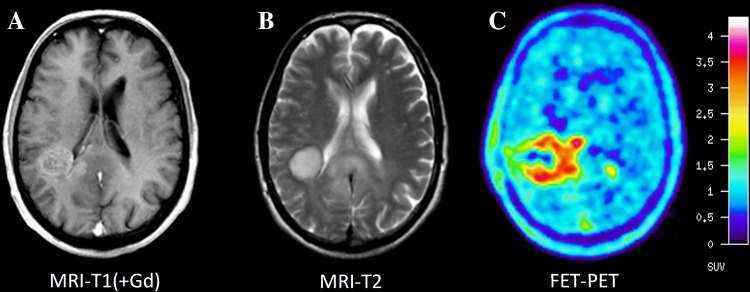

For PET, a number of studies have explored the spatial correlation of histopathological findings with amino acid uptake and provided evidence that the solid tumour mass of gliomas typically shows increased amino acid uptake and detects tumour extent more reliably than standard MRI [57–62] (Fig. 2). The improved delineation of tumor extent is one of the most important advances in brain tumor diagnostics provided by amino acid PET, but it has to be considered that a fraction of approx. 5% of all gliomas, especially low-grade gliomas, do not accumulate radiolabeled amino acids [35]. Nevertheless, amino acid PET is clearly superior to the standard MRI and the property of amino acid PET to detect tumour extent has been used in many studies for treatment planning, especially in tumor resection and radiation therapy [63–73]. In contrast, only a few studies have investigated the diagnostic value of PWI for the detection of brain tumour extent [74, 75]. Those studies observed elevated rCBV beyond the contrast-enhancing volume indicating that tumour infiltration might also be detected by PWI. A biopsy-controlled study reported that rCBV regionally correlates with both cell and microvessel density within gliomas [76]. Another biopsy-controlled study demonstrated that rCBV correlated with cell proliferation in high-grade gliomas but a correlation of rCBV with tumour cell density could not be confirmed [74]. These studies suggest that rCBV mapping allows only very limited conclusions with regard to tumor extension. While some earlier studies comparing amino acid uptake and rCBV observed similarities between MET uptake and rCBV abnormalities in gliomas [77, 78], more recent publications reported on considerably larger tumour volumes in amino acid PET than in rCBV maps and a poor spatial overlap [23, 79–82] (Figs. 3, 4; Table 1). Furthermore, rCBV mapping exhibited a lower lesion-to-brain contrast and a highly variable background noise as compared with amino acid PET [23, 79]. Another hybrid PET/MRI study reported that artifacts due to susceptibility differences between bone and air, iron accumulations, and blood degradation products hampered interpretation of the rCBV signal in the tumour area in 56% of the patients [80]. Thus, amino acid PET appears to be superior to rCBV mapping for the detection of the extent of cerebral gliomas and interpretation of rCBV maps appears to be more challenging than with amino acid PET.

Fig. 4.

Comparison between MRI and 18F-DOPA PET of a patient with an astrocytoma. A non-enhancing (A), FLAIR positive (B) left temporo-thalamic lesion is seen, corresponding to 18F-DOPA uptake (C) above the physiological radioactivity of the basal ganglia. In contrast, rCBV map (D) fails to show increased tumor perfusion. An anaplastic transformation was observed 3 months later, characterized by contrast enhancement and increased rCBV (images not shown)